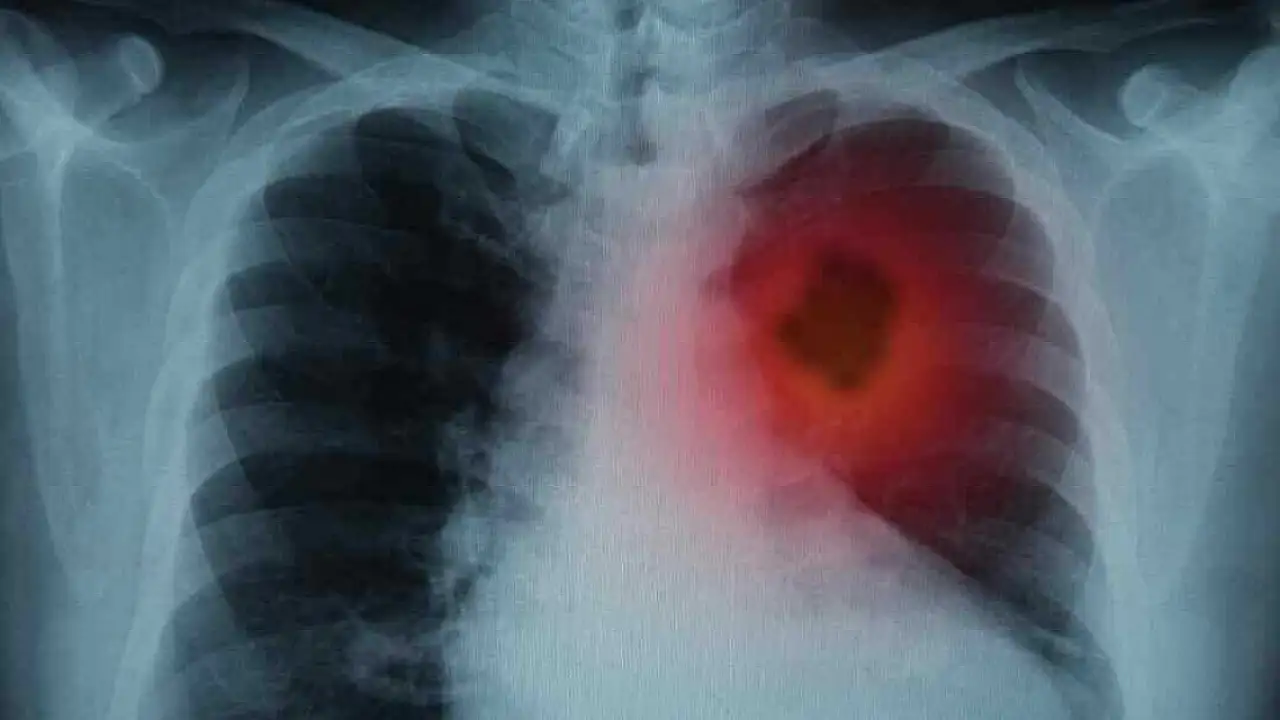

Akciğer dokusundaki normal hücreler kontrol dışı çoğalarak kitle yani tümör oluşturduğunda akciğer kanseri meydana geliyor. Kitle büyüyerek önce çevre dokulara, dolaşım yoluyla da beyin, karaciğer gibi diğer organlara yayılıyor. Akciğer kanserinin erken dönemde belirti vermeyebileceğini ifade eden Göğüs Hastalıkları Uzmanı Dr. Aygün Gür, "Geçmeyen ve giderek artan öksürük, öksürükle ağızdan kan veya kanlı balgam çıkarmak, nefes darlığı, göğüs ağrısı, ses kısıklığı, halsizlik, iştahsızlık, geçmeyen ve tekrarlayan akciğer enfeksiyonu gibi belirtiler görülebilir" şeklinde konuştu.

Tanı için akciğer röntgeni, bilgisayarlı tomografi gibi görüntüleme yöntemleriyle kitle saptandıktan sonra, kitleye hangi yolla ulaşarak örnek alınacağı belirleniyor. Kanserin türü ve evresi belirlendikten sonra tedavinin planlandığını belirten Gür, "Akciğer kanserinde erken tanı çok önemli. Tedavi şansını artırdığı gibi ölüm oranını da azaltmaktadır. Tedavi; hastanın yaşı, klinik durumu, kanserin tipi, evresi gibi faktörler ışığında planlanarak cerrahi, kemoterapi veya radyoterapi programlarının biri veya birkaçı bir arada uygulanır" dedi.